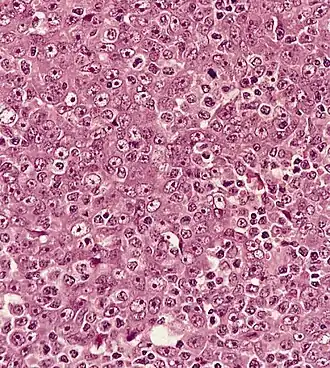

dans un ganglion lymphatique (apparence syncytiale, noyau vésiculaire proéminent)

Histologie

L'OMS divise ce cancer en trois sous-types : carcinome à cellules kératinisées, carcinome à cellules non kératinisées, carcinome indifférencié.

Les types 2 et 3 sont associés avec l'infection à virus d'Epstein-Barr.